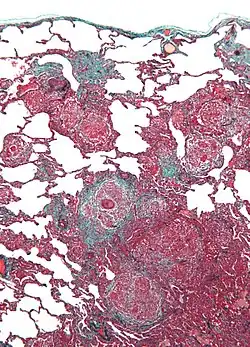

Als Vogelhalterlunge (auch: Vogelzüchterlunge oder Taubenzüchterkrankheit) wird eine Alveolitis exogen-allergischer Ursache bezeichnet. Sie kann in akuter oder in schleichend-chronischer Form auftreten.

Bei den Allergenen, die diese Krankheit auslösen, handelt es sich um tierische Proteine, die im Staub und Kot von Vögeln auftreten. Federn in Daunen-Textilien kommen ebenfalls in Frage. Diese Allergene führen zu einer entzündlichen Reaktion des Lungengewebes, die durch eine Immunkomplexreaktion vom Typ III verursacht wird.